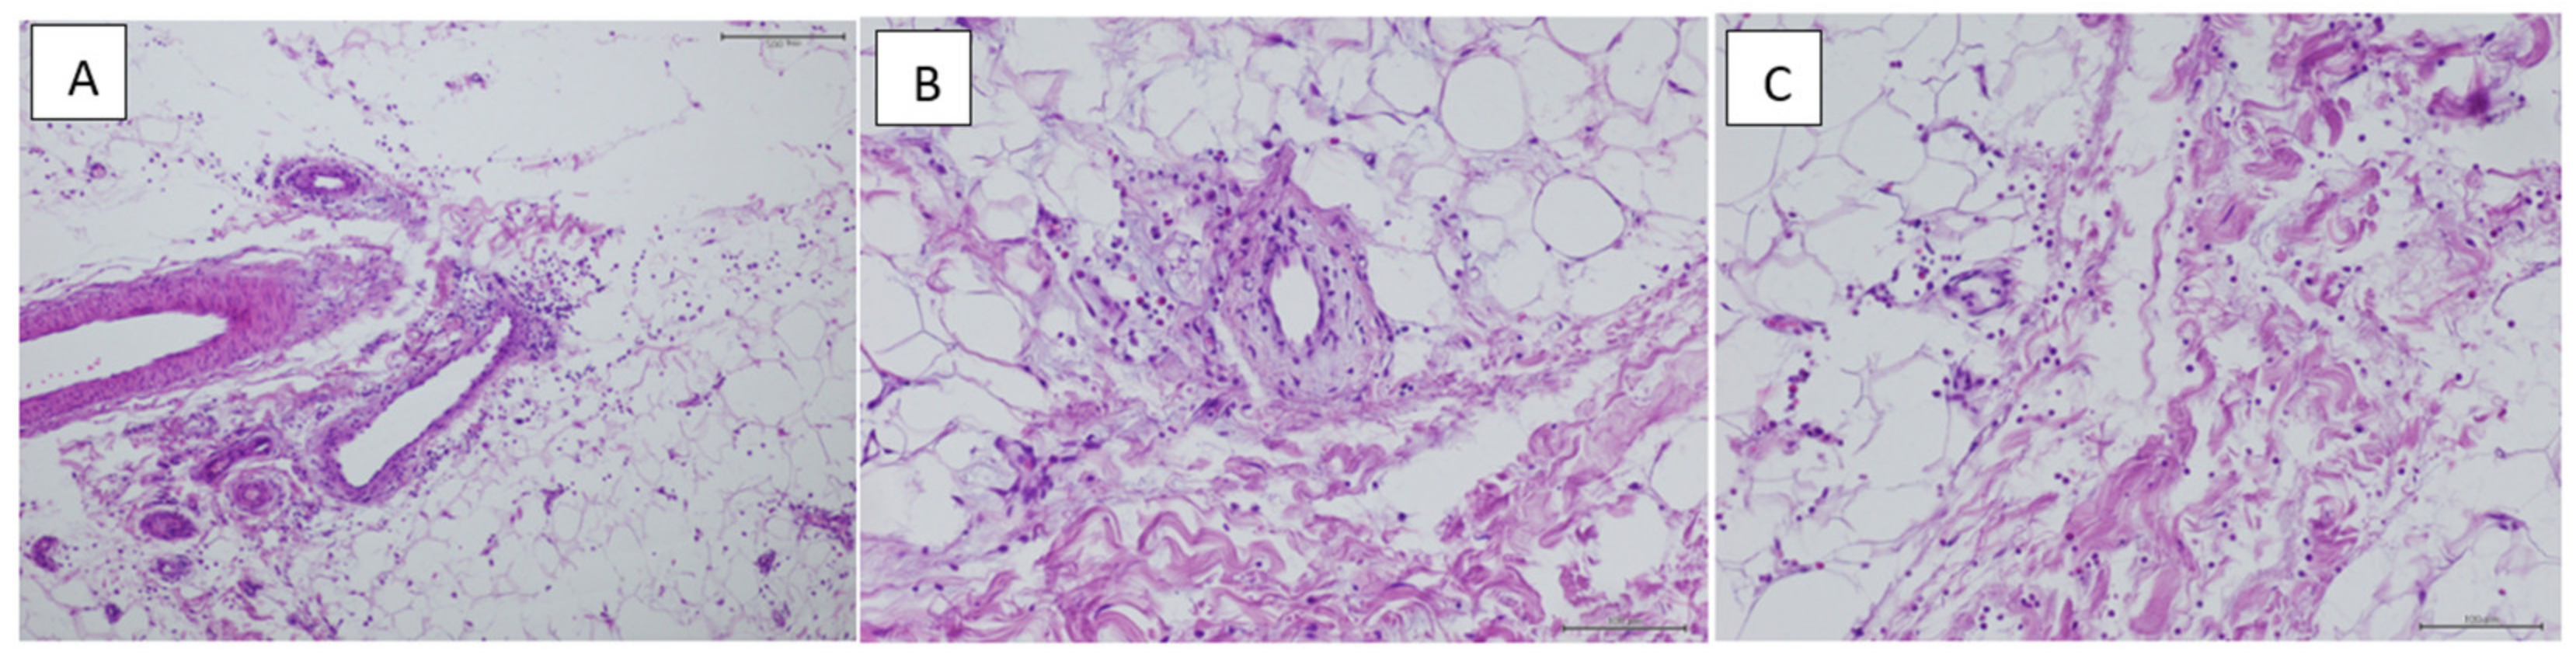

Histology